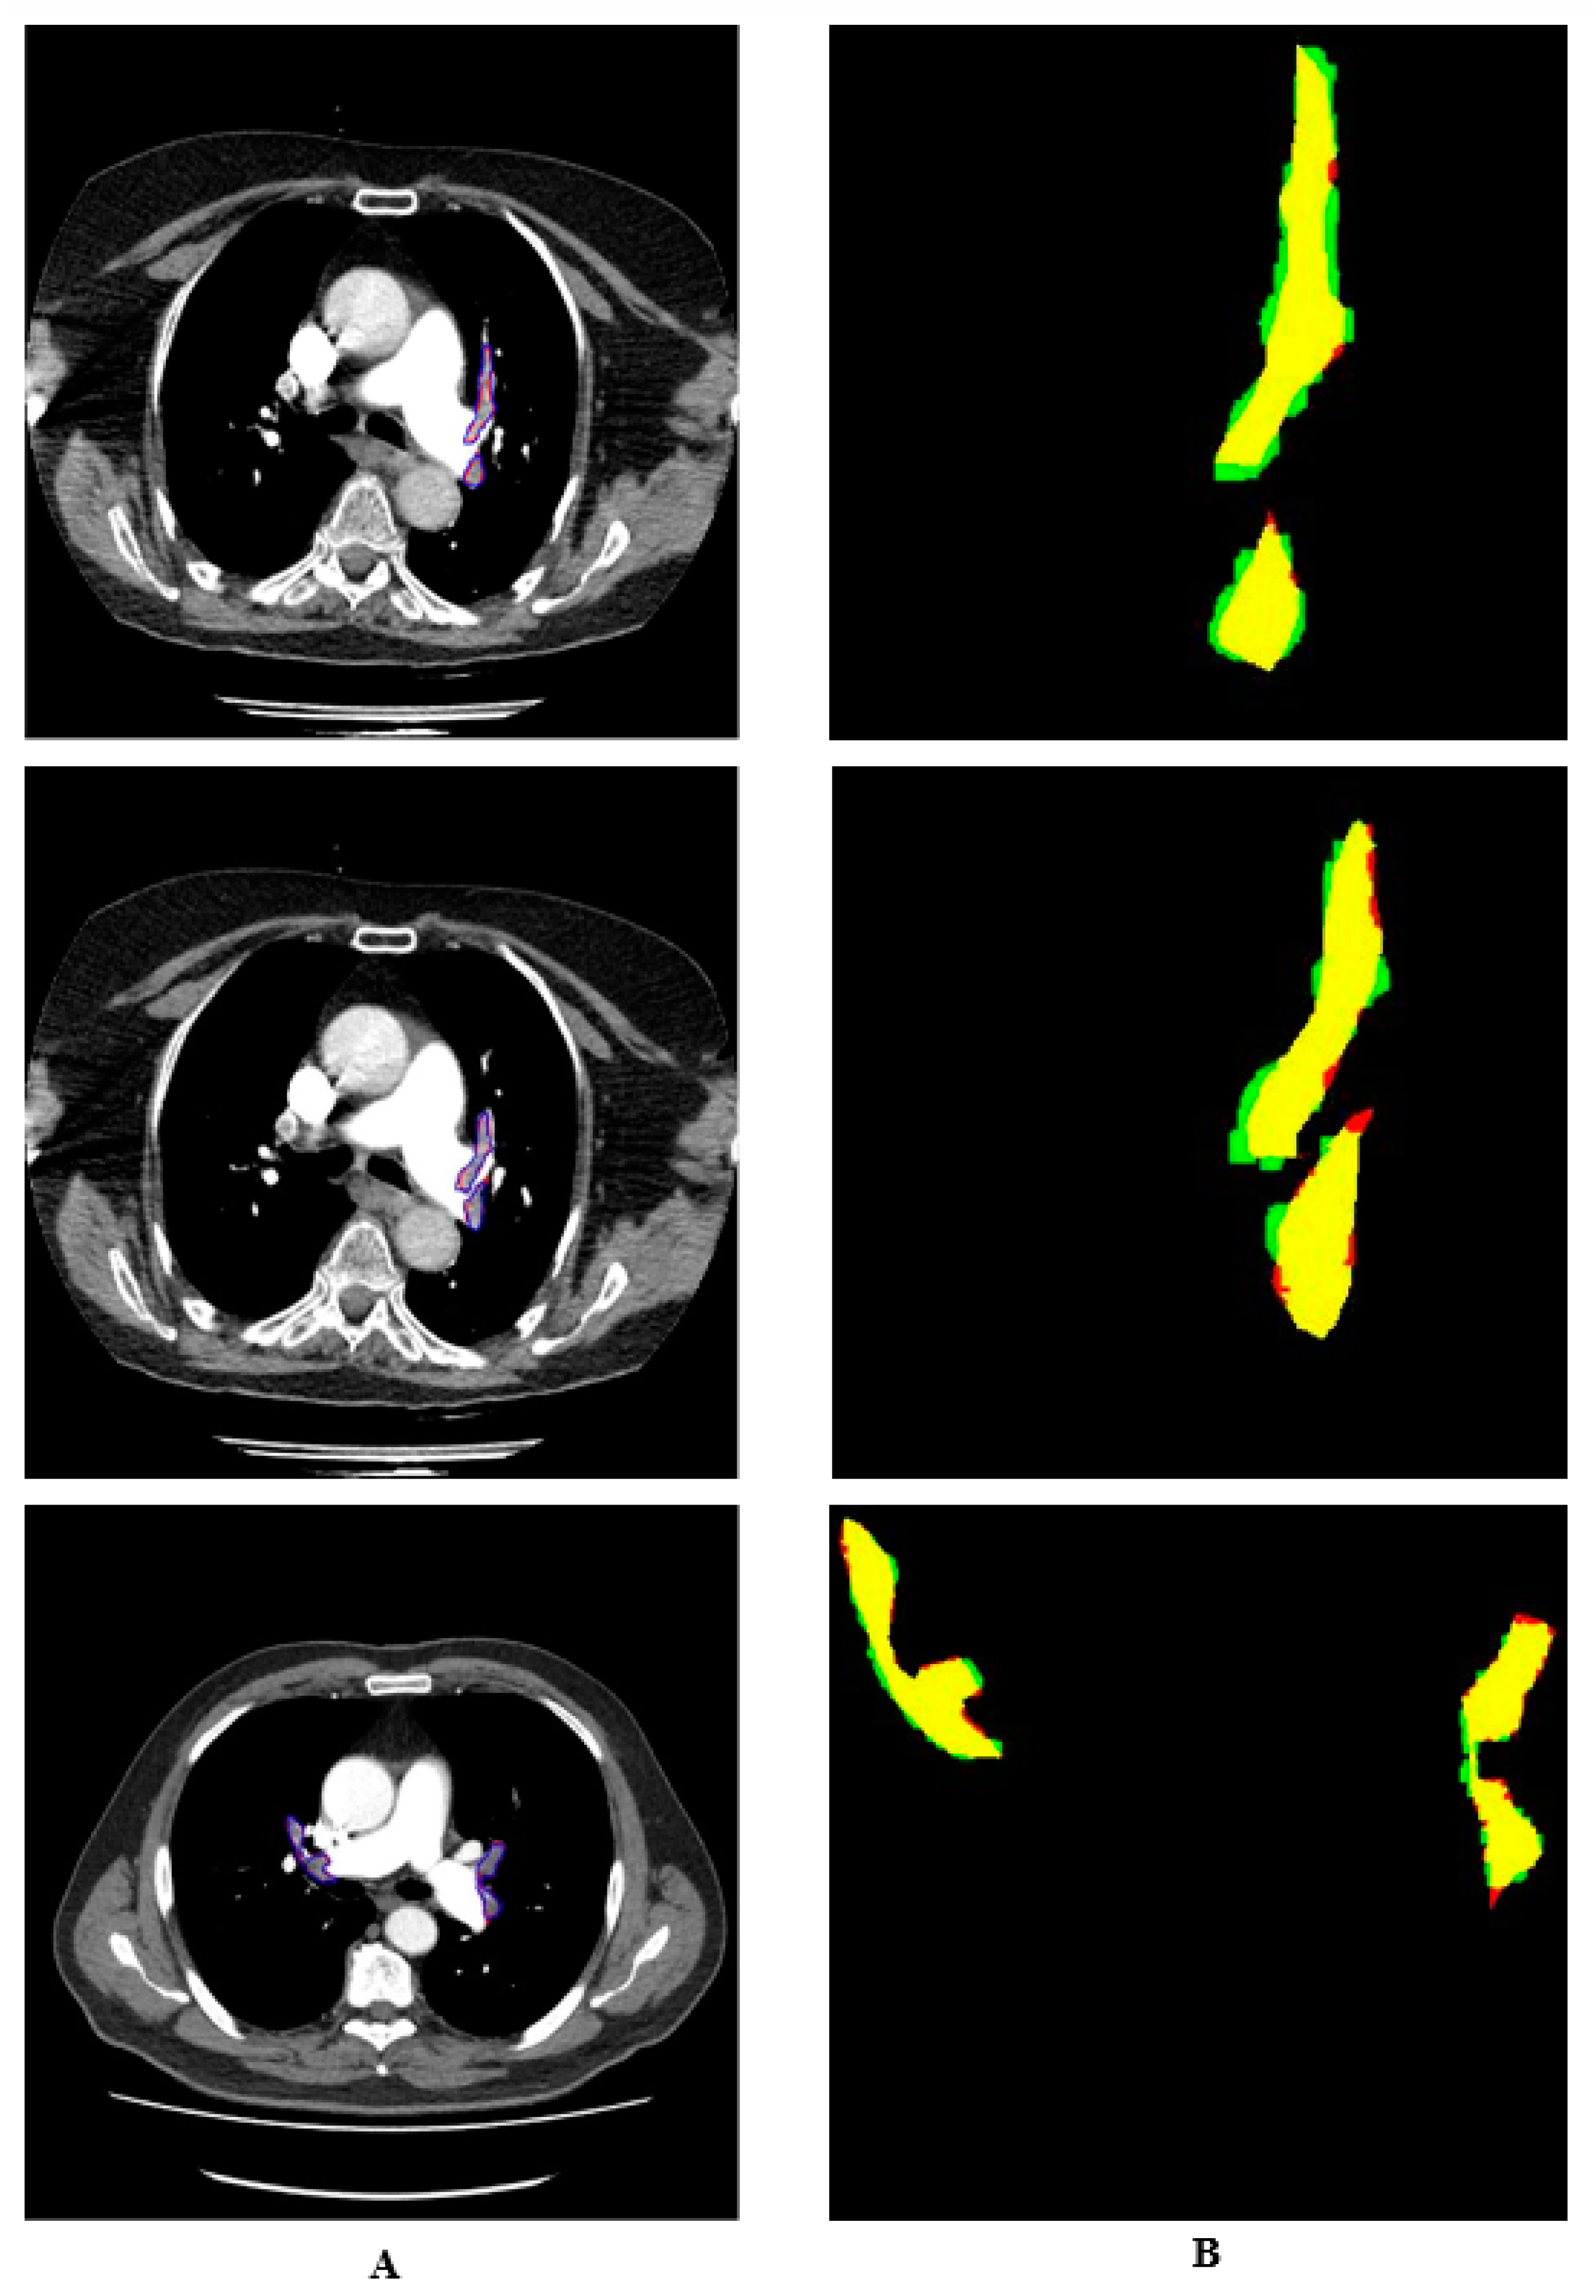

Manual and automatic segmentations are shown in colour in Figure 7. The regions identified by the expert but not detected by the system are shown in red. The regions detected by the system as PE but not by the doctor are shown in green. The pixels belonging to the PE detected in both ways are shown in yellow. It is seen that the proposed system detects PE with a high performance.

Figure 7. Colored drawing of manually and automatically segmented PE.